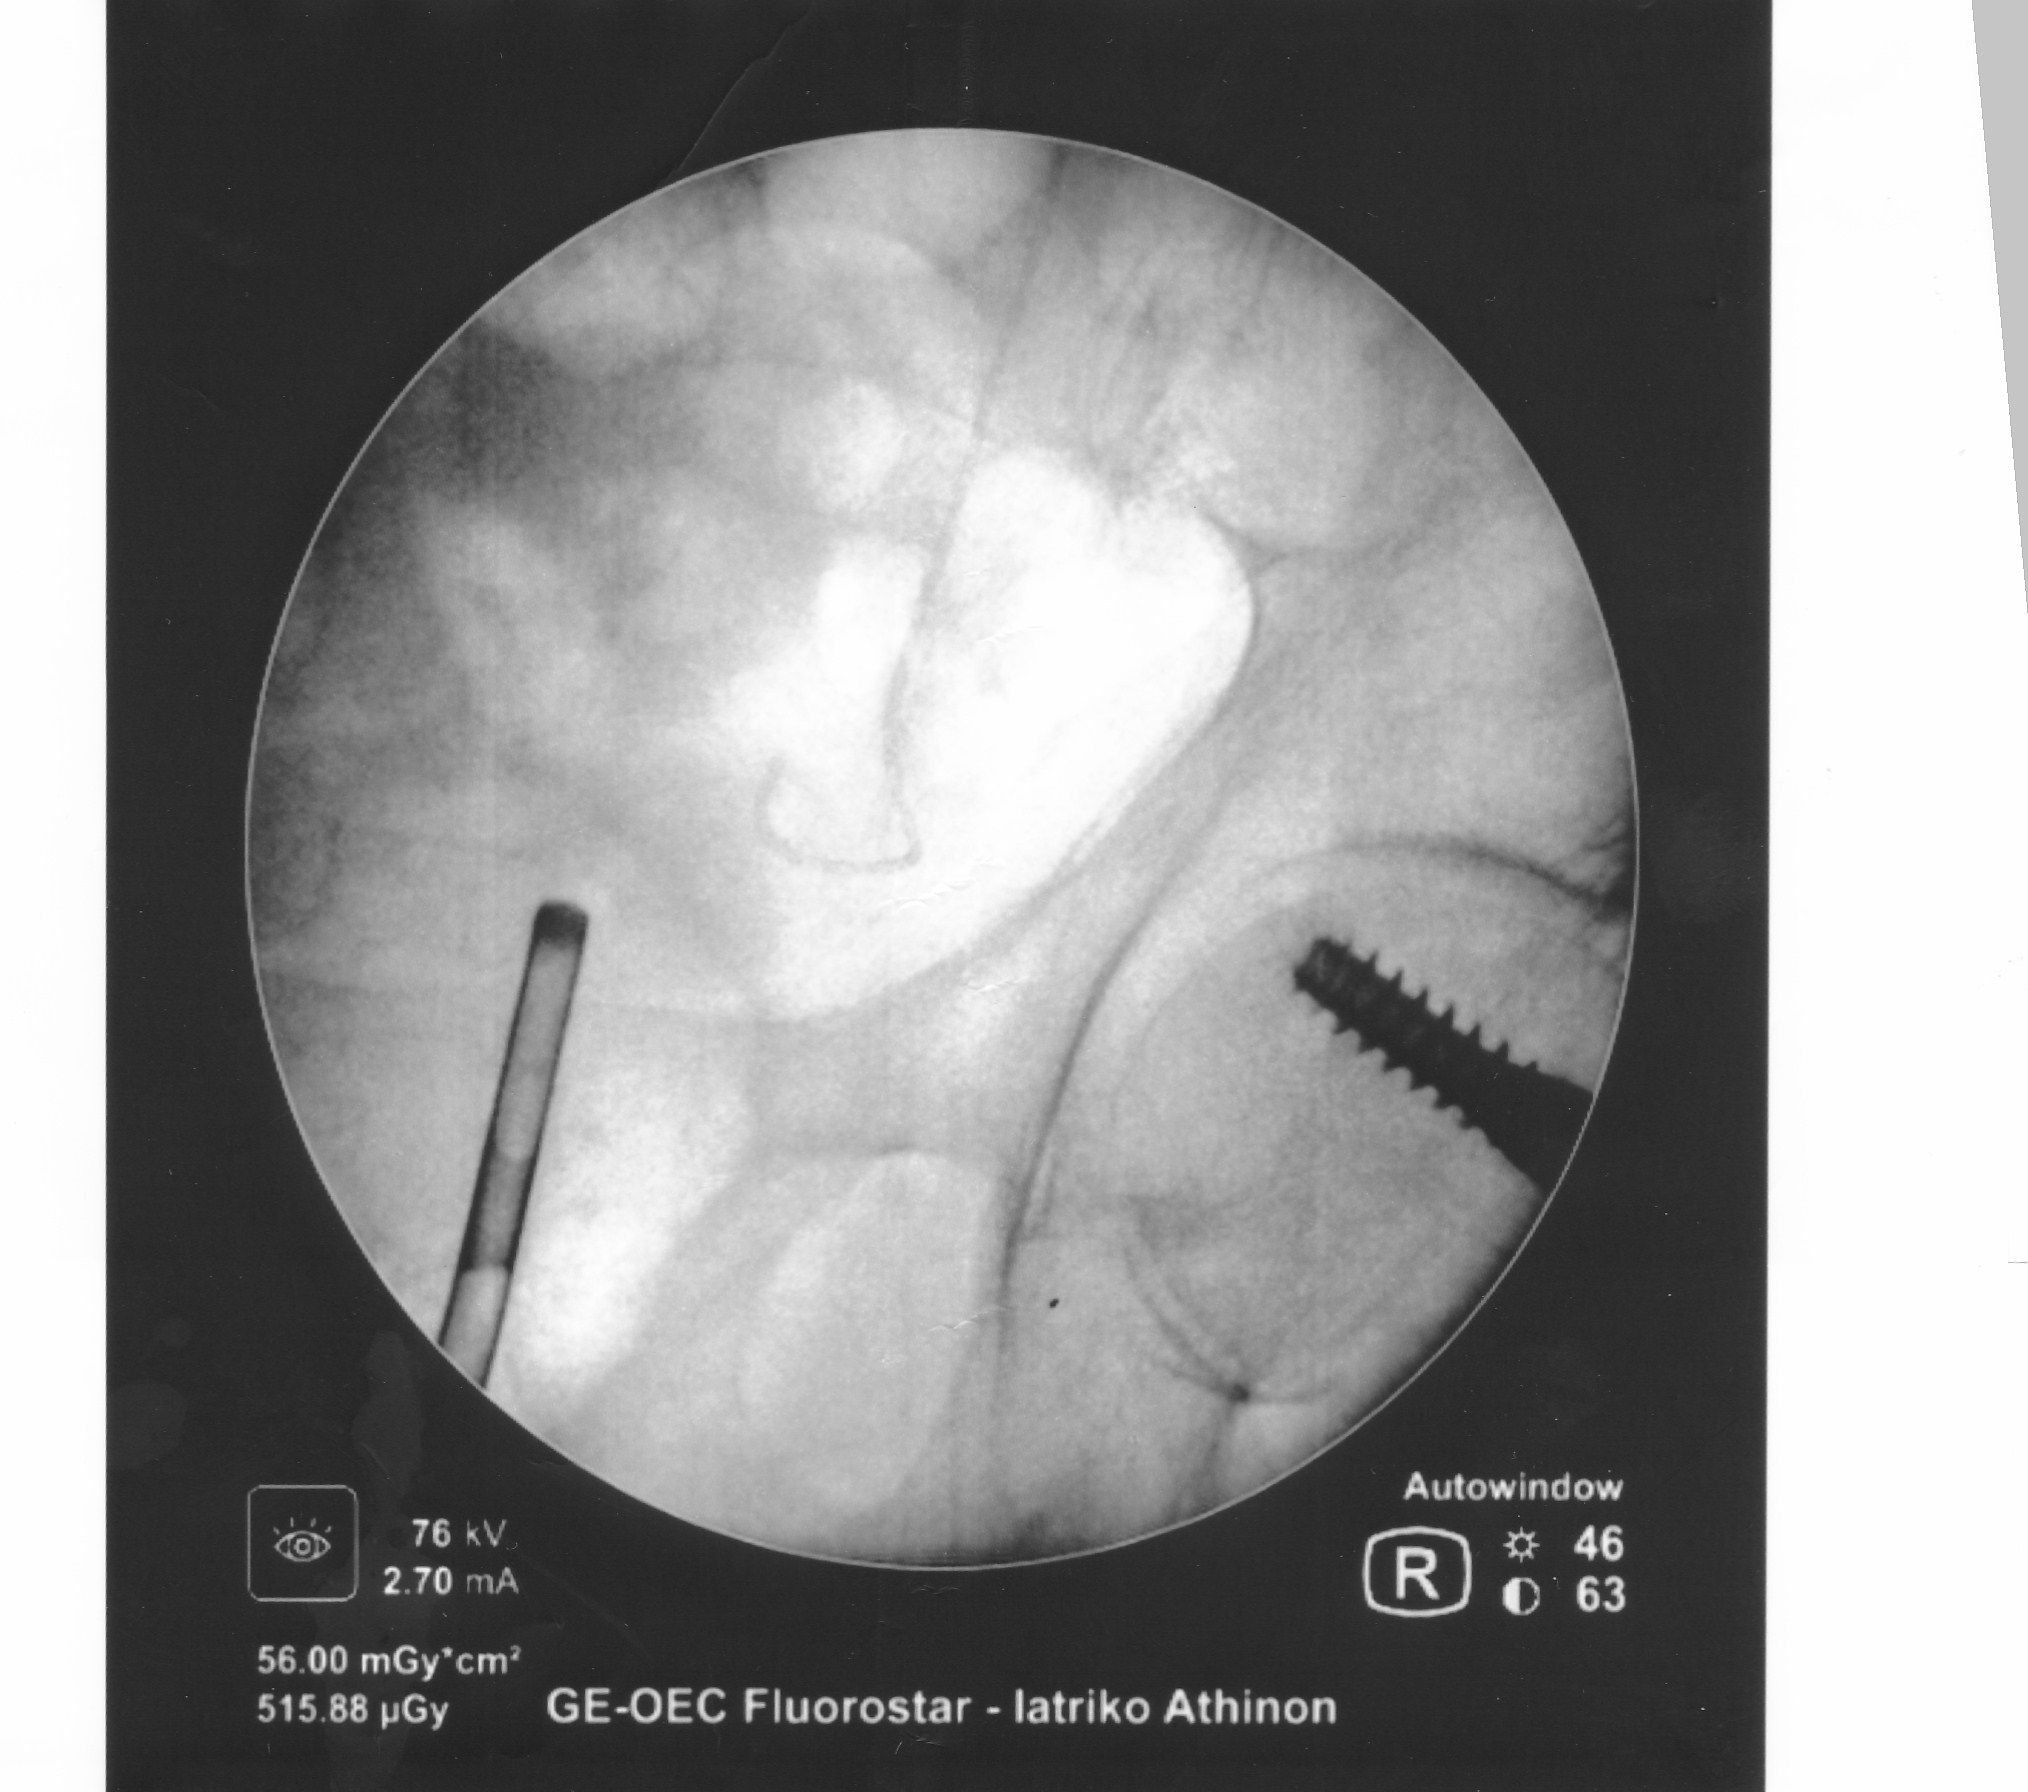

Είναι γνωστό ότι η Λιθίαση (πέτρες) της ουροδόχου κύστεως (σχήμα 1) θα πρέπει να αντιμετωπίζεται με σύγχρονες Ενδοσκοπικές τεχνικές.

Ενδοσκοπική Holmium Laser Κυστεολιθοτριψία